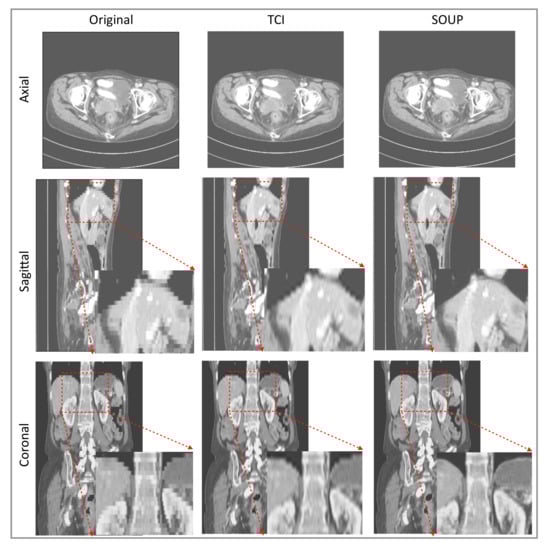

We also apply our scale-attention SR model to CT data. Figure 6 and Figure 7 show the SR-interpolated (SOUP) and conventionally interpolated images on abdominal and pelvic CTs. It is clear from both examples that the SR-interpolated results achieve significantly higher quality than the conventionally interpolated ones in regard to the edges, textual details, and blurring. Those comparisons demonstrate that our scale-attention SR model (SOUP) is a widely generalizable tool for different sampling factors and various applied imaging modalities, which paves the way for more advanced medical image interpolation through deep-learning SR.

Figure 6.

Example of SR interpolation on CT with a sampling factor equal to 4.8. Edges and textual details are better resolved by SR. Blurring is reduced. TCI: tricubic interpolation.

Figure 7.

Another example of SR interpolation on CT data with a sampling factor equal to 5.72. TCI: tricubic interpolation.